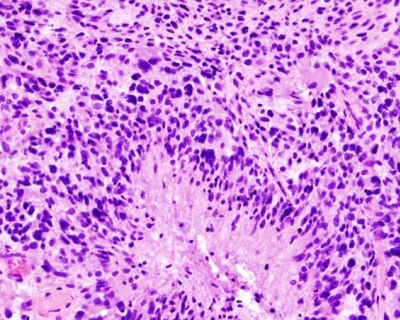

Rakovina mozku